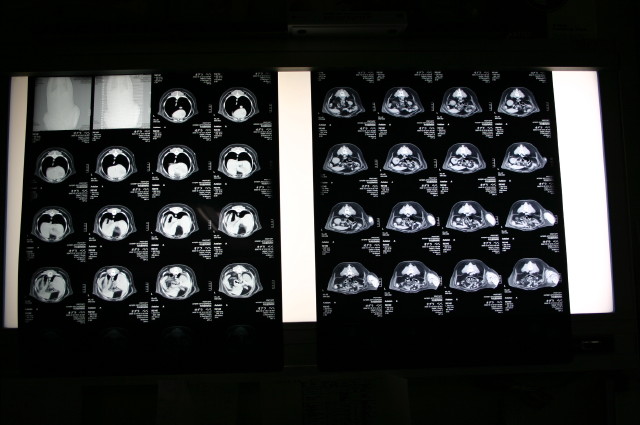

(背骨が下)たぶんこれが肺だと思います。違ったらすみません(^^ゞ

【2】胆のうに胆泥が少したまっているが(エコーでも指摘された)、悪さをするような状態ではなく、今すぐ何かをしなくてはならないような状態ではない。問題ないでしょうとの事。

ポインタの先の濃い白いところが胆泥。わかりますか?

4枚目の写真は、CTで撮ったレントゲンみたいなもの。背骨も“フセ”状態の股関節もくっきり写っている

普通のレントゲンは“一点”から写すので裾は多少ゆがみというか、伸びたような状態に写るけれど、CTは“輪切り”で写すのでゆがみがでないらしい。

5枚目の写真は、今回撮ったCTの一部。

[左]が頭側で、胴体を輪切りにしながら徐々におしり側が写っている。

これが、先生のところのPCのだと、濃度をかえたりしながら、体の中を流れるように見ることができる。